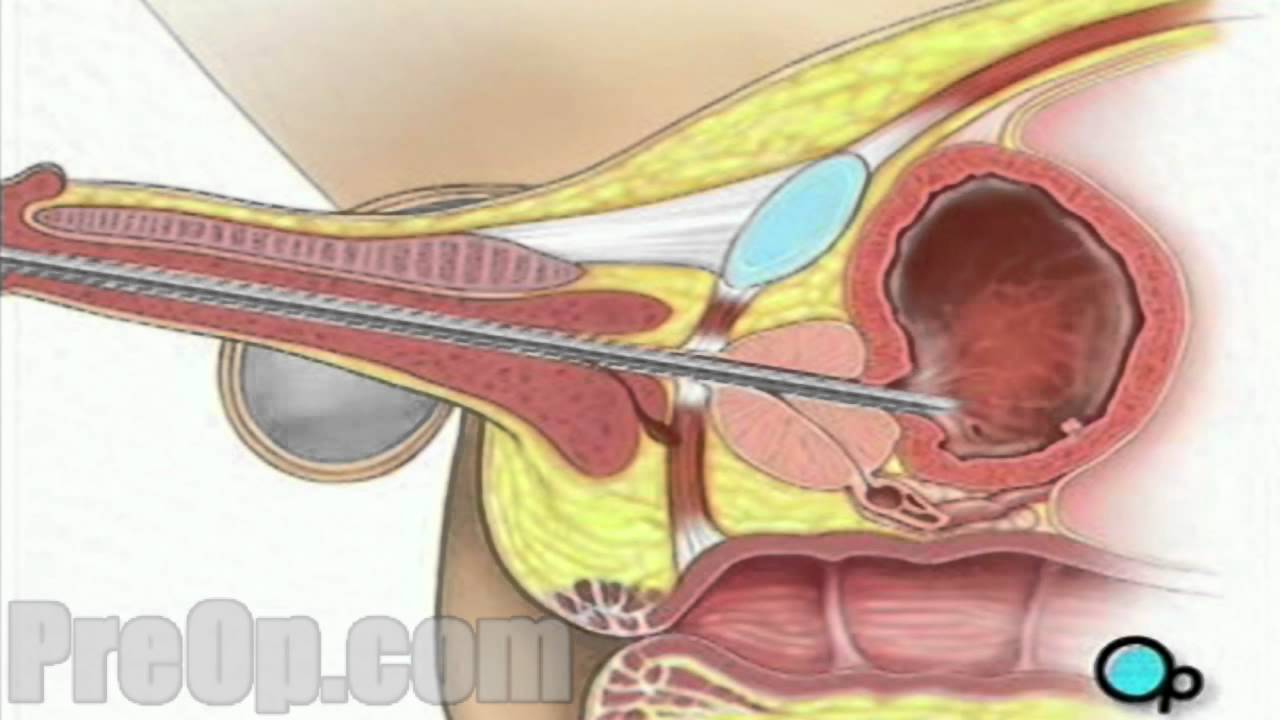

Urethral intercourse or coitus per urethram is sexual penetration of the female urethra by an object such as a penis or a finger. It is not the same thing as urethral sounding, the act of inserting a specialized medical tool into the urethra as a form of sexual or fetishistic activity.

Urethral intercourse or coitus per urethram is sexual penetration of the female urethra by an object such as a penis or a finger. It is not the same thing as urethral sounding, the act of inserting a specialized medical tool into the urethra as a form of sexual or fetishistic activity.

Urethral intercourse. Urethral intercourse or coitus per urethram is sexual penetration of the female urethra by an object such as a penis or a finger. It is not the same thing as urethral sounding, the act of inserting a specialized medical tool into the urethra as a form of sexual or fetishistic activity.

It is not the same thing as urethral sounding, the act of inserting a specialized medical tool into the urethra as a form of sexual or fetishistic activity. The untrained insertion of foreign bodies into the urethra carries a significant risk that subsequent medical attention may be required.